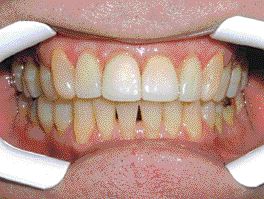

Implantology: Expect the Unexpected!

FIGURE 29--Another 'HAPPY ENDING.'

Most of the time, when a patient comes in for implant treatment and you have done all of the pre-treatment work-up (complete and thorough) you might probably expect the case to go to completion with little (or no) complications. As routine as this might be in a high volume implant practice, it is not always … Read more